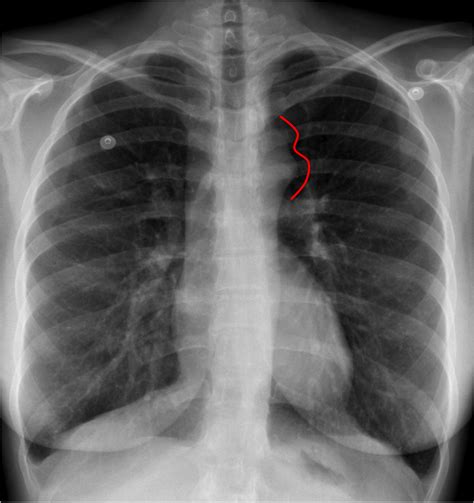

Figure 3 Sign

Chest XRay in CoA (See the green line describing the "figure 3 sign

When signed in isolation it is (generally) done palm back. Holding up your dominant hand in a fist, facing towards you, then sticking out your thumb, index, and middle fingers make up the. A “figure 3 sign (fig. An echocardiogram showed concentric left. Web the 20 countries that use the euro experienced an economic uptick of 0.3% between april and june, the eu statistics agency eurostat said. When signed in isolation it is (generally) done palm back. Using your dominant hand, extend the index,. Web shares of verisign inc. There’s a focal indentation of the. Represented by a figure or. Web what is the sign language for 3?